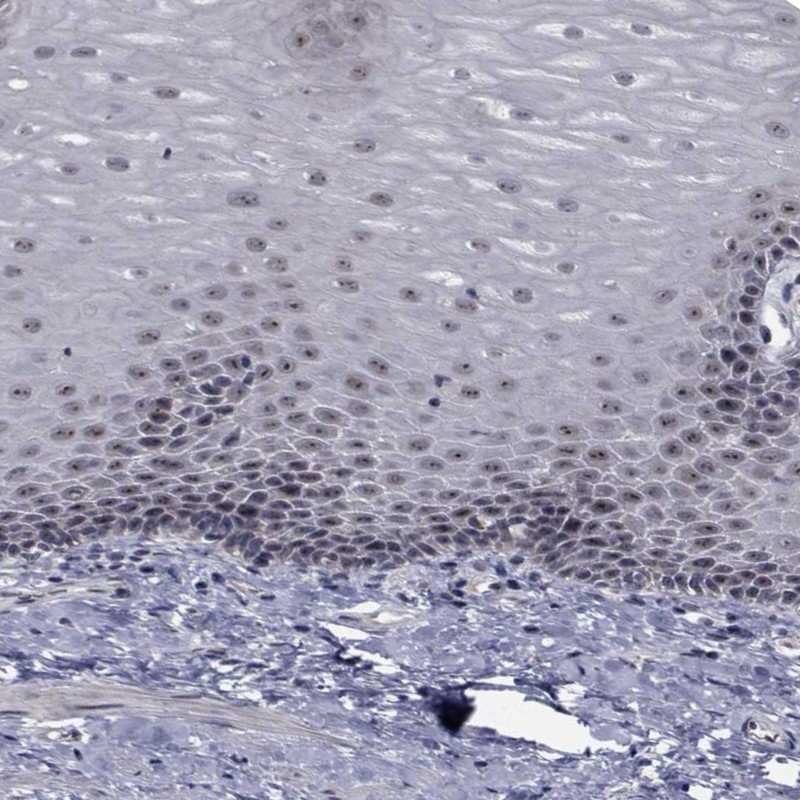

Immunohistochemical staining of human esophagus shows moderate nuclear and nucleolar positivity in squamous epithelial cells.